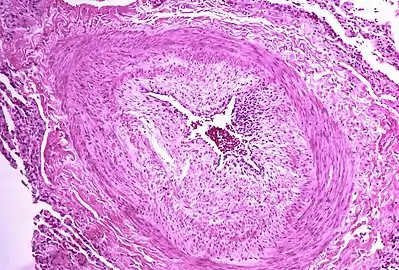

Right ventricle (on left side)

Micrograph showing arteries in pulmonary hypertensive with marked thickening of the walls.

The pathogenesis of pulmonary arterial hypertension (WHO Group I) involves the narrowing of blood vessels connected to and within the lungs. This makes it harder for the heart to pump blood through the lungs, much as it is harder to make water flow through a narrow pipe as opposed to a wide one. Over time, the affected blood vessels become stiffer and thicker, in a process known as fibrosis. The mechanisms involved in this narrowing process include vasoconstriction, thrombosis, and vascular remodeling (excessive cellular proliferation, fibrosis, and reduced apoptosis/programmed cell death in the vessel walls, caused by inflammation, disordered metabolism and dysregulation of certain growth factors).[24][25] Over time, vascular remodeling causes the affected blood vessels to become progressively stiffer and thicker. This further increases the blood pressure within the lungs and impairs their blood flow. In common with other types of pulmonary hypertension, these changes result in an increased workload for the right side of the heart.[11][26] The right ventricle is normally part of a low pressure system, with systolic ventricular pressures that are lower than those that the left ventricle normally encounters. As such, the right ventricle cannot cope as well with higher pressures, and although right ventricular adaptations (hypertrophy and increased contractility of the heart muscle) initially help to preserve stroke volume, ultimately these compensatory mechanisms are insufficient; the right ventricular muscle cannot get enough oxygen to meet its needs and right heart failure follows.[11][25][26] As the blood flowing through the lungs decreases, the left side of the heart receives less blood. This blood may also carry less oxygen than normal. Therefore, it becomes harder and harder for the left side of the heart to pump to supply sufficient oxygen to the rest of the body, especially during physical activity.[27][28][19]